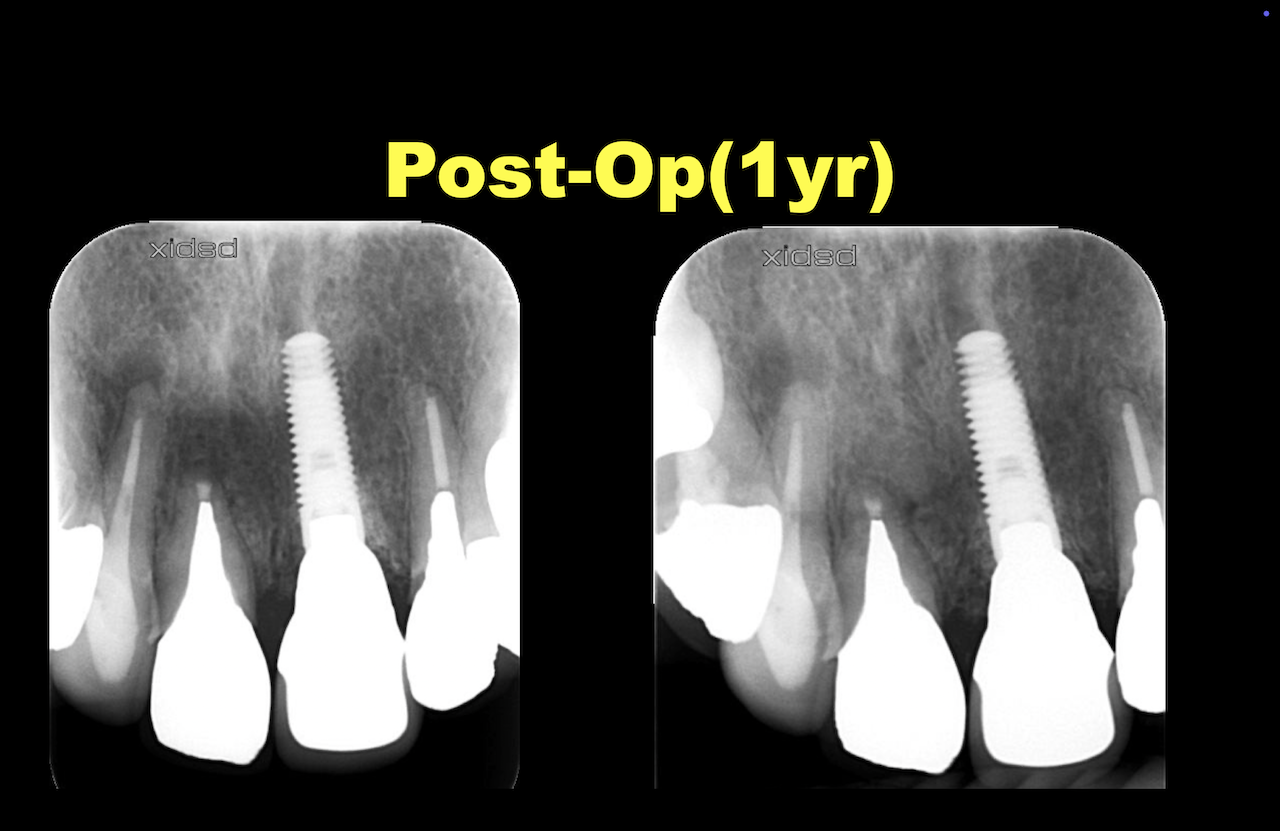

ここから1年経過して以下のようになった。

歯周病がなければこのようになる確率が90%である。

それは何度も言うように、私がでなく過去の研究で、だ。